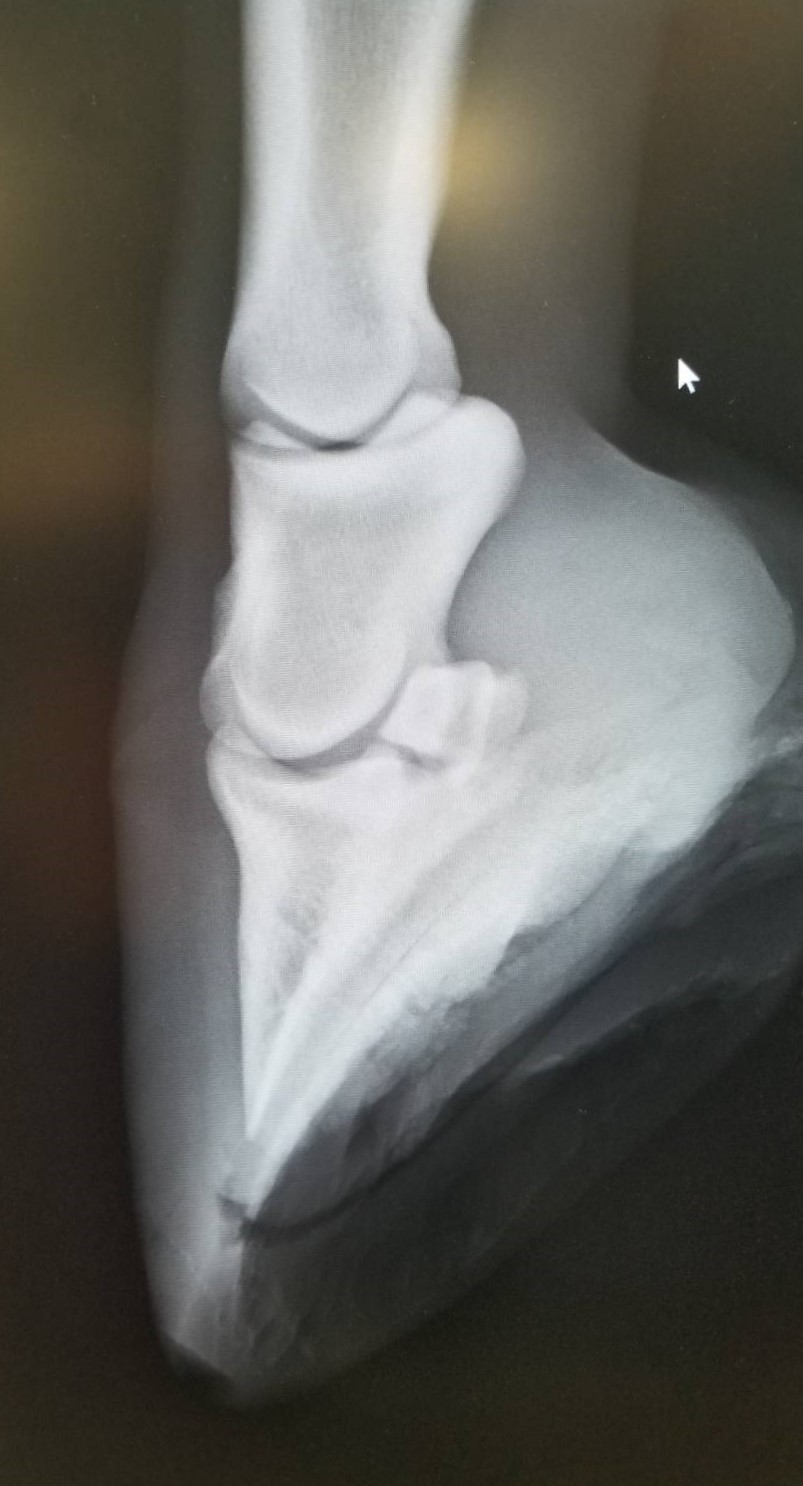

6月9日に左前脚を挫跖し、いったんは回復したものの、6月18日に再び左前の歩様が悪くなりました。調べたところ、蹄内にフレグモーネの症状が見られ、発熱し、白血球の数値も上がっていました。再度の挫跖か、蹄から菌が入ったものと考えられます。その後、熱と白血球の数値は落ち着きましたが、しばらくは左前脚を地面につけるのを嫌がるほど痛がっていました。6月28日のレントゲン検査の結果、中に溜まった膿が抜ける部分がなく、蹄骨の下を通って蹄球から抜けるという珍しい症例でした。そのため、膿が通り抜けた部分が空洞になって蹄底が上下に動く形になり、古い蹄の部分が当たり痛みが出ていたものと推測されます。

現在はACS(アドバンスクッションサポート)を蹄底に充填し、空洞を押さえつけるような形にしていることから、痛みはなく、歩様も正常です。今後は特に治療の必要はなく、蹄が伸びて、蹄の中の状態が改善されるのを待つだけという状況です。獣医師、装蹄師の診断では、蹄鉄を履かせて乗り出すまでに至るには1ヶ月程度必要とのことです。